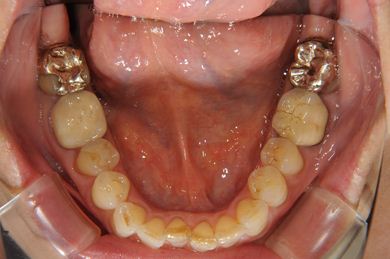

部分矯正治療+セラミック治療

| 性別/年齢 | 女性 / 54歳 | ||||||||||||||||||||||||||||||||

| 主訴 | 下の前歯のゆがみが気になり、相談。 | ||||||||||||||||||||||||||||||||

| 治療方針 | 上顎前歯の叢生を部分矯正にて審美的回復を行い、上顎前歯はラミネートベニアにて審美的回復を行う。 | ||||||||||||||||||||||||||||||||

| 治療内容 | 唇側部分矯正(ホワイト)、オールセラミックラミネートベニア8本 | ||||||||||||||||||||||||||||||||